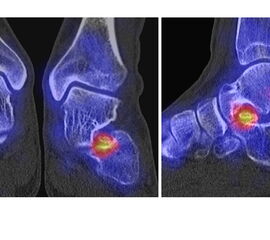

Abbildung 9.2.a bis d: SPECT/CT zur Beurteilung der Knochen-Vitalität bei einer Talusnekrose. 5 Jahre zuvor während der Arbeit war die Patientin beim Treppensteigen umgeknickt und zog sich Außenbandrupturen zu. Nachfolgend persistierende Beschwerden mit Entwicklung einer Talusnekrose. Frage nach Vitalität und Ausdehnung der Nekrose. Deutliche bis intensive Traceranreicherung im Bereich des linken Talus. Im SPECT/CT befindet sich der Hypermetabolismus in allen Abschnitten des Talus mit relativer Aussparung eines sich demarkierenden Fragmentes lateral, was die laterale Talusschulter umfasst, die Größe beträgt transversal ca. 23 x 16 mm. In diesem Fragment relativ homogene Skelettstruktur, diese Befunde weisen auf eine trophische bzw. nekrotische Störung des Talus hin mit einem sich demarkierendem Fragment, welches die laterale Talusschulter beinhaltet.

Die Abbildung 9.3.a bis d zeigt ein weiteren Fall mit einer SPECT/CT zur Beurteilung der Knochen-Vitalität bei einer Talusnekrose. Die Bilder zeigen eine abgelaufene Nekrose mit zystischen Resorptionen des linken Talusdoms bei nachweislich erhaltener Vitalität der umgebenden Knochenabschnitte aufgrund des hier überall deutlich erhöhten Knochenmetabolismus (= inkomplette Restitutio). Aufgrund der nachweislich erhaltenen Vitalität konnte erfolgreich eine Knochen-Transplantation erfolgen.Deutlich geringer ausgeprägte nekrotische Veränderungen auch im rechten Talusdom bei hier weitgehend erhaltenen Gelenkkonturen.